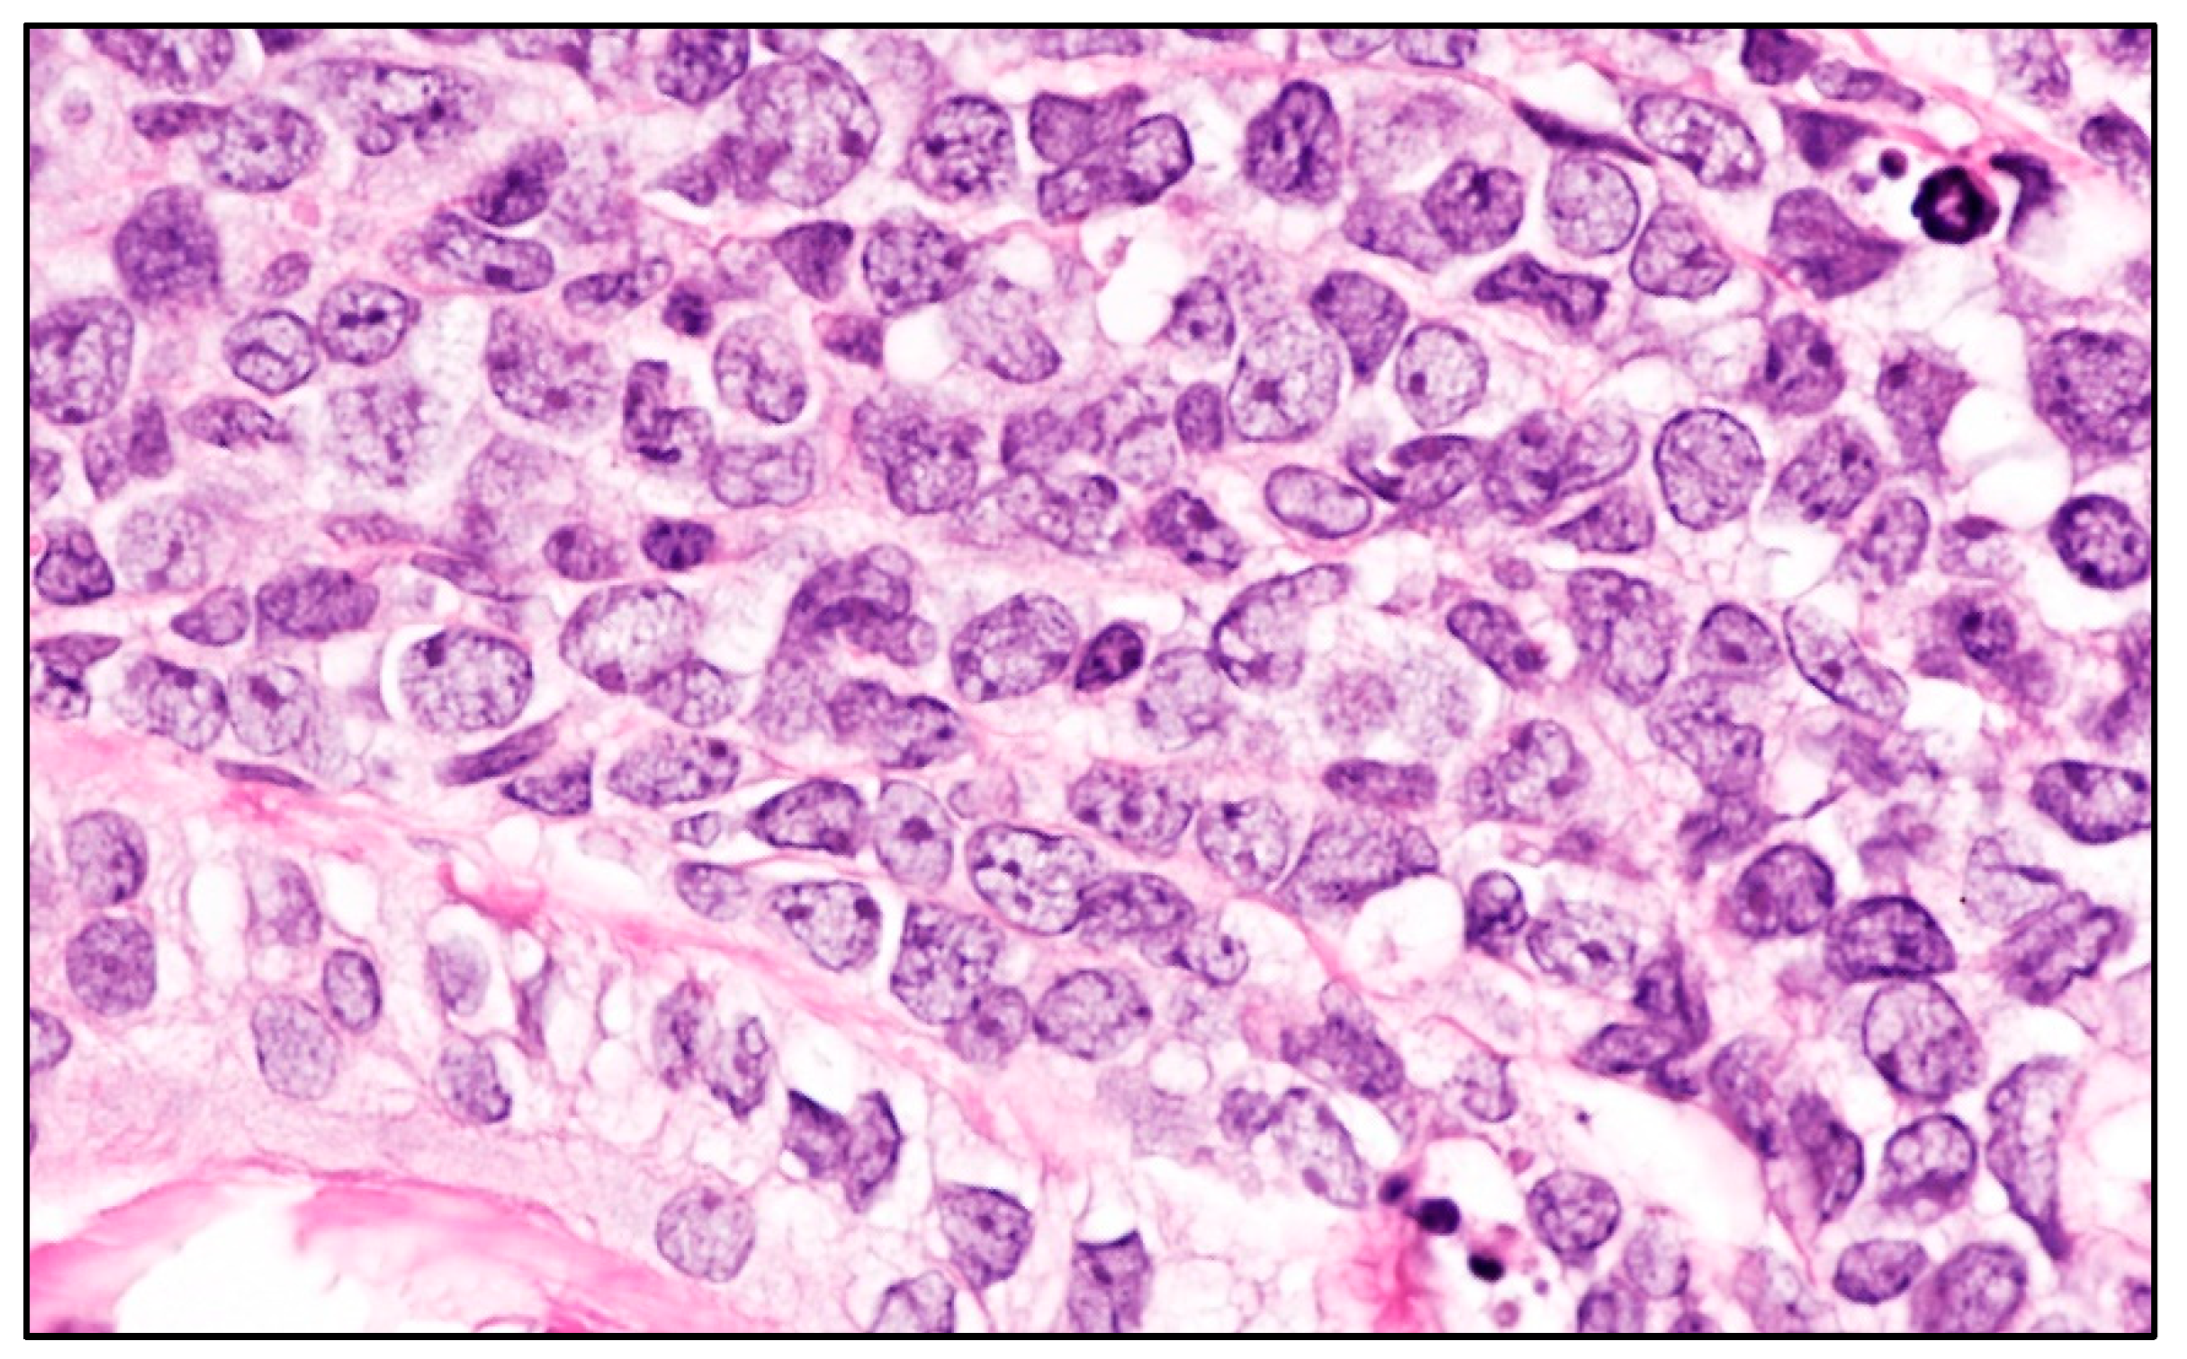

| Blastoid MCL | M:F = 3:1; late sixties | Solitary/multiple papules or nodules; often on extremities. Often previous history of MCL; skin lesions in recurrent and progressive disease | Diffuse dermal and subcutaneous tissue infiltrate; no epidermis and Grenz zone involvement. Monomorphic, medium-sized cells, round/oval nuclei, dispersed chromatin, inconspicuous nucleolus | Mature, naïve B-lymphocytes | CD20+, cyclin D1+, TdT−, CD3−, CD5+ (CD5 loss in 25-28% of blastoid MCL); aberrant expression of CD10, BCL6, CD23; TP53 overexpressed; high Ki67 | Poor. Intensive CT and immunotherapy plus ASCT; recently, anti CD19 CART cells, venetoclax, ibrutinib, acalabrutinib |

| B-LBL | F:M = 2:1 children young adults | Often solitary, firm papule or nodule on head and neck. Skin lesions in 15-33% of B-LBL; skin lesions associated with systemic disease | Dense dermal infiltrate; no epidermis and Grenz zone involvement; uniform, small, medium-sized cells, round/oval/convoluted nuclei, fine chromatin, barely visible nucleoli, scarce basophilic cytoplasm; numerous mitoses | Precursor B- lymphocytes | TdT+, CD34+, CD10+, PAX5+, cCD79alpha+, CD19+, CD22+, high Ki67 | Good prognosis in 70% of cases with B-lineage ALL-type. Multiagent CT. |

| T-LBL | M:F = 3:1 children young adults | Multiple papules or nodules on head and neck (83.3%); different anatomic areas in 41.7%. Skin lesions rare in T-LBL (4.3% of cases); skin lesions secondary to T-LBL in mediastinum or lymph nodes | Histology identical to B-LBL | Precursor T-lymphocytes | TdT+, CD34+, CD1a+, CD99+, CD117+, cCD3+, sCD3+, CD2+, CD5+, CD7+, aberrant cCD79alpha+, aberrant myeloid markers+ | Cutaneous T-LBL are rare, but with a worse outcome compared to cutaneous B-LBL despite multiagent CT. |